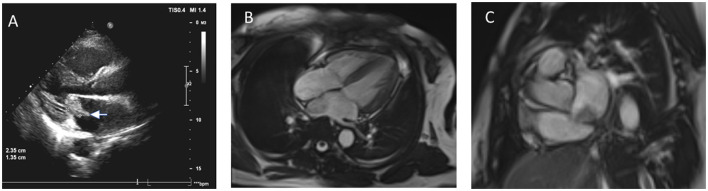

心房黏液瘤是一种罕见的良性肿瘤,可引起多种并发症,包括脑梗死。我们提出一个病例52岁的女性患者谁发展脑梗死引起的心房粘液瘤。患者成功手术切除了肿瘤,并对梗死进行了相应的治疗。然而,术后15个月,患者出现了新的神经系统症状。影像学检查显示多发性脑转移,与肿瘤细胞播散的可能性一致。这种罕见的并发症强调了心房黏液瘤切除术后长期监测的重要性。脑转移的发生虽然罕见,但应在随访中予以考虑,特别是在发生心房黏液瘤相关栓塞事件的患者中。我们的病例强调了即使在最初成功的手术干预后,脑黏液瘤转移的可能性,强调了对此类患者进行全面随访和警惕监测的必要性。

Atrial myxoma is a rare benign tumor that can cause a variety of complications, including cerebral infarction. We present a case of a 52-year-old female patient who developed cerebral infarction caused by an atrial myxoma. The patient underwent successful surgical resection of the tumor, and the infarction was managed accordingly. However, 15-months post-surgery, the patient developed new neurological symptoms. Imaging studies revealed multiple cerebral metastases, consistent with the possibility of seeding of tumor cells. This rare complication emphasizes the importance of long-term monitoring after the resection of atrial myxomas. The occurrence of metastasis in the brain, though rare, should be considered in follow-up care, particularly in patients who have had embolic events related to atrial myxomas. Our case highlights the potential for cerebral myxoma metastasis even after initial successful surgical intervention, underscoring the need for comprehensive follow-up and vigilant monitoring of such patients.